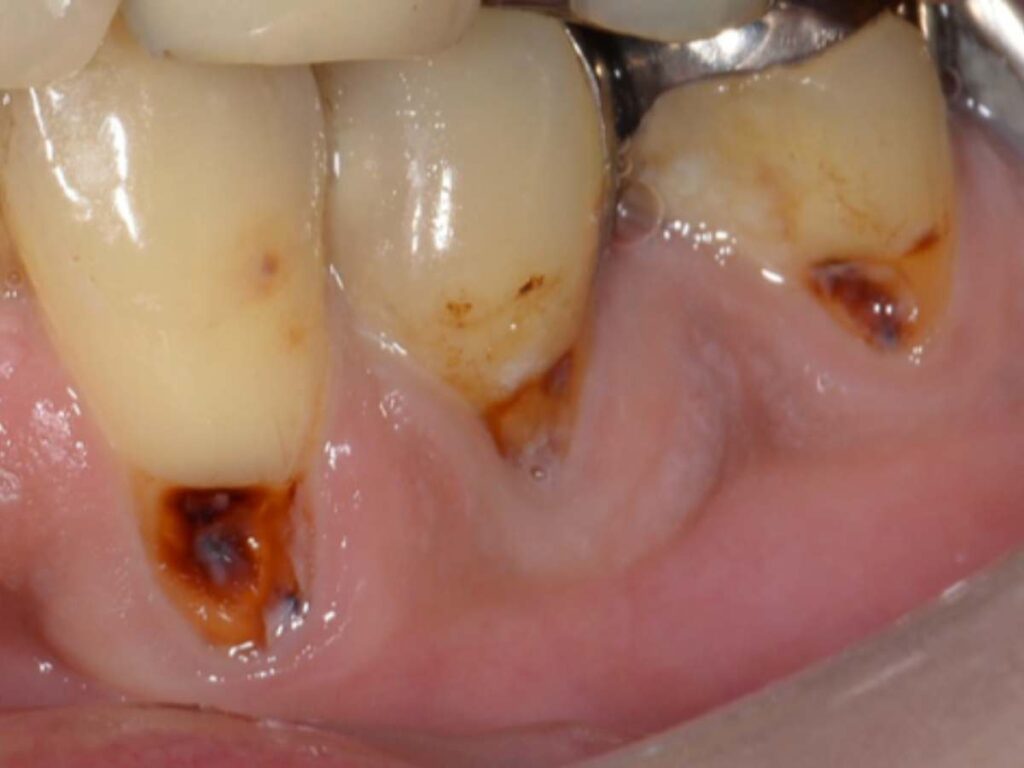

今回の症例は下顎犬歯〜小臼歯に生じた歯肉退縮部の根面う蝕でした。歯ぐきが下がったことで歯根が露出し、その部分に虫歯が発生してしまったケースです。そこで今回は単純に虫歯を詰める治療ではなく、歯周形成外科(歯肉移植術)を併用した治療を行いました。

✔ 根面う蝕(虫歯)を丁寧に除去

✔ 露出している歯根を歯肉移植で被覆

✔ 強く安定した角化歯肉を再建

- 術前側方面観

- 術前正面観